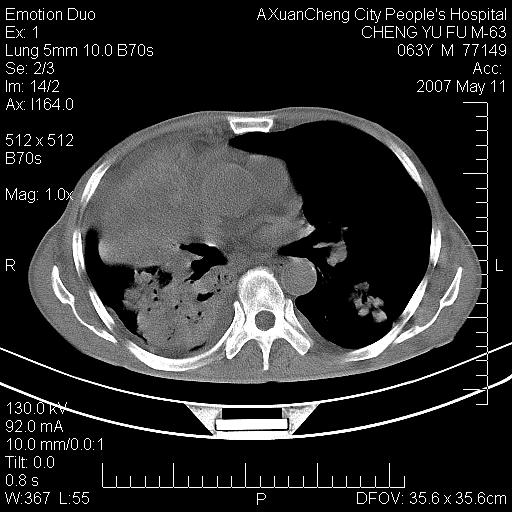

以下是引用小初学者在2007-5-11 19:32:00的发言:[br]1、首先考虑干酪性肺炎支气管播散[br]2、支气管肺泡癌待排

以下是引用zhangzhongshou在2007-5-11 19:30:00的发言:[br]细支气管肺泡癌可能性大。